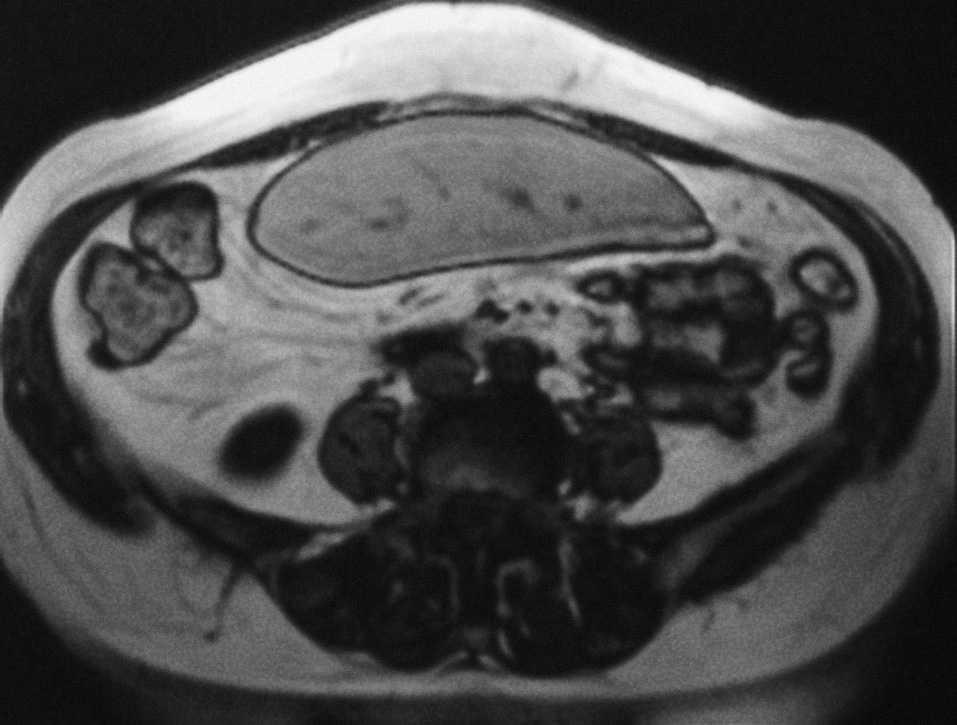

Mujer de 67 años sin antecedentes de interés, que presenta tos irritativa y a la que se detecta una masa hepática en la tomografía computarizada torácica realizada para descartar patología pulmonar. La exploración clínica y la analítica resultan anodinas. La resonancia magnética abdominal demuestra una masa quística hepática bien delimitada, de 15 x 11 x 12 cm, que ocupa todo el lóbulo hepático derecho (fig. 1), con contenido homogéneo, sugestiva de quiste hidatídico, y una hipertrofia compensadora marcada de los segmentos II y III, que miden 20 x 12 x 7 cm (fig. 2 y 3). Se practicó quistoperiquistectomía subtotal abierta. Al año de seguimiento se encuentra asintomática.

Fig. 2.